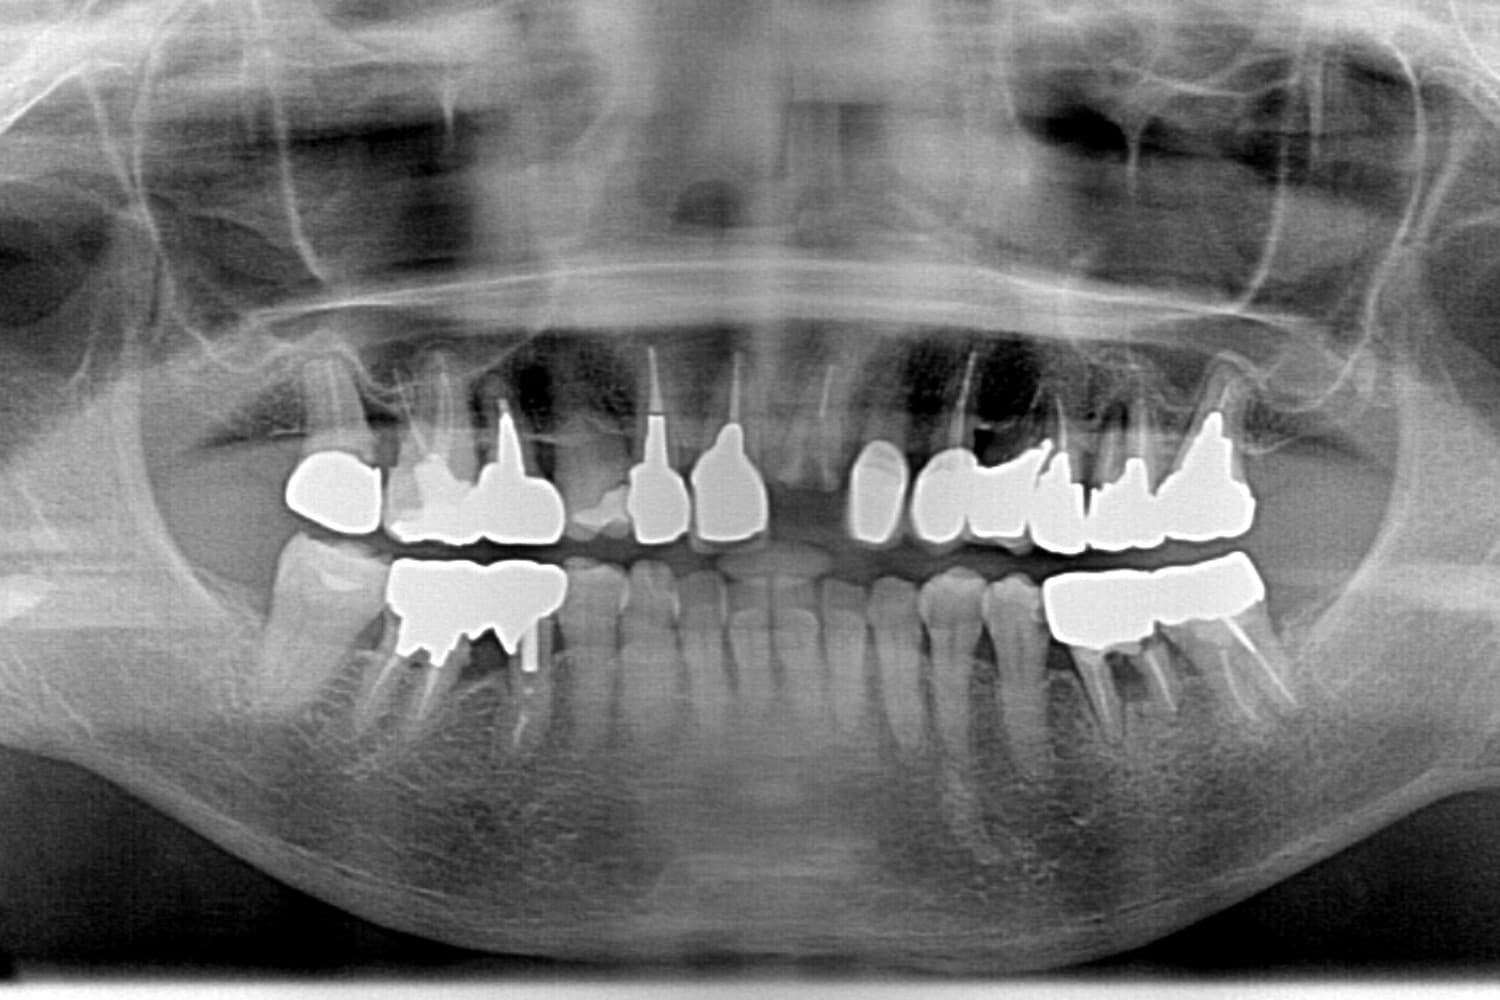

Before

他院で総義歯を入れたが、噛むと上の義歯が落ちて使えない。インプラント相談希望。